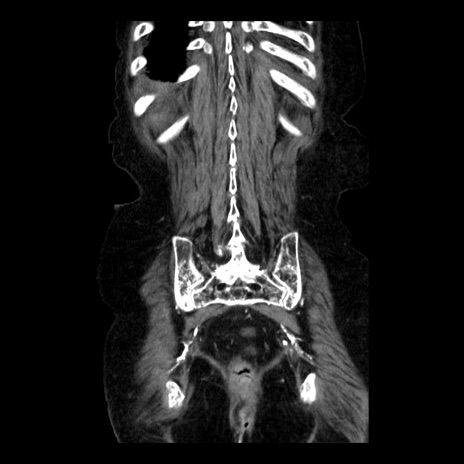

症例14(冠状断像)

【症例】 90歳代女性

【主訴】 腹痛・嘔吐

【現病歴】今朝から左側腹部痛を認めた。 経過観察していたが、嘔吐を認めたため来院。

【既往歴】 子宮癌術後

【身体所見】 意識清明、BP 127/54mmHg、P 98bpm Sp02 95%(RA)、BT 35.8°C、腹部平坦・軟腸ぜん動音聴取良好、右下腹部圧痛(+) 反跳痛なし

【データ】WBC 9800、CRP 0.46